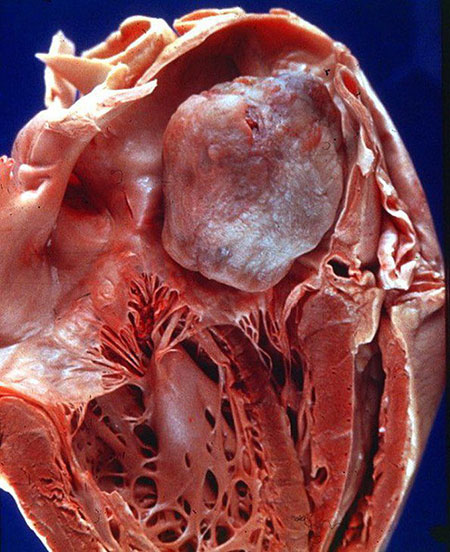

میگزوم قلبی یک تومور است که بر قلب تاثیر میگذارد. این شایعترین تومور غیرسرطانی اولیه قلب است. اندازه میگزومها متغیر است. برخی از آنها به اندازه 1 سانتیمتر قطر دارند، در حالی که برخی دیگر میتوانند تا 15 سانتیمتر رشد کنند. حدود 74% از تمام میگزومها در دهلیز چپ، که اتاق بالایی سمت چپ قلب است، ایجاد میشوند. حدود 18% در دهلیز راست شکل میگیرند. بیشتر میگزومها به عنوان میگزومهای دهلیزی شناخته میشوند زیرا در اتاقهای بالایی قلب ایجاد میشوند. باقیمانده (8%) در بطنها (اتاقهای پایین قلب) شکل میگیرند.

میگزومها معمولاً از سپتوم دهلیزی رشد میکنند. این دیواره عضلانی است که دهلیز چپ و دهلیز راست را از هم جدا میکند. آنها معمولاً با یک پدیکل (پایهای که اجازه میدهد میگزوم حرکت کند) به سپتوم متصل میشوند. تومور میتواند حرکت کرده و گاهی به یکی از دریچههای قلب بیفتد و باعث مشکلات در جریان خون شود.